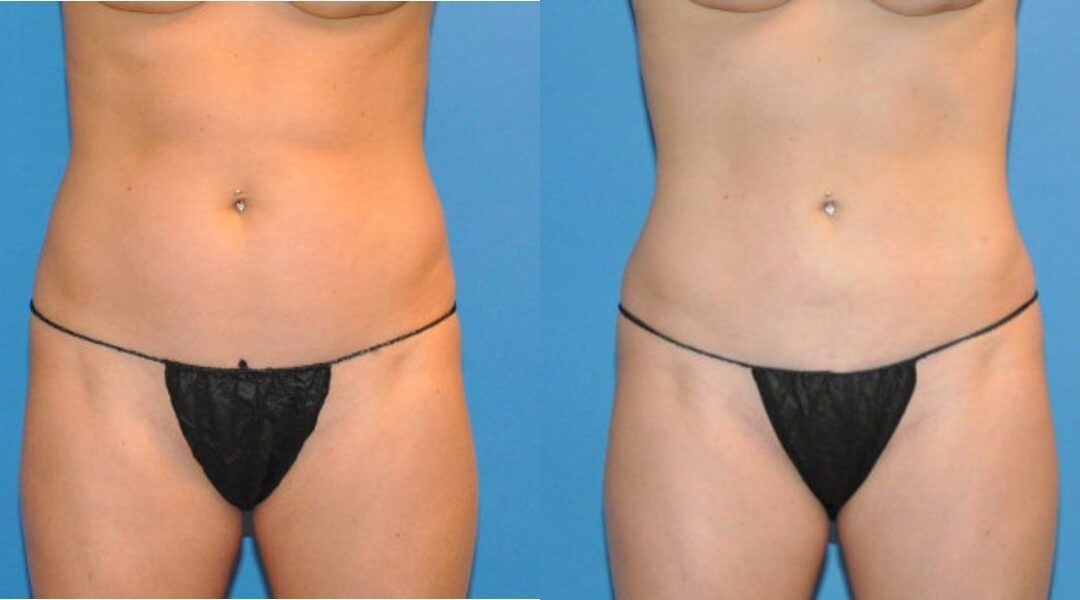

This patient desired improvement in the mild fattiness that she had along the abdomen and waist regions. She is an excellent liposuction candidate because of her youthful and elastic skin quality. She was treated with tumescent liposuction to the upper and lower abdomen, waist and hips. Her post operative result is depicted at one year after surgery, when all of the post operative swelling common with liposuction has resolved. Her cosmetic result is smooth and uniform with good improvement in the treated regions.